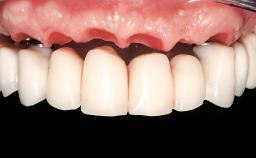

Immediate Loading of Eight Implants in the Maxilla and Six Implants in the Mandible and Final Restoration with Three-Unit and Four-Unit FDPs

German Gallucci, Jean-Pierre H Bernard, Urs C Belser

Prosthesis Type FDP

SAC Level Complex

Defining Characteristics Fully edentulous upper jaw to be rehabilitated with an implant-borne fixed dental prosthesis

Loading Protocol Immediate